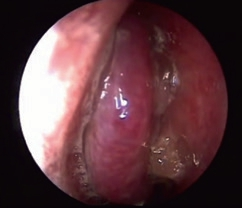

Eine kugelige homogene Verschattung in der Höhle wird im Rahmen der zahnmedizinischen und HNO-Behandlung häufig beobachtet (Abb. 5). Schmerz oder Druckgefühl werden in der Regel nicht angegeben. Bei diesen Retentionszysten handelt es sich oft um Zufallsbefunde, die bei bis zu 14% der Bevölkerung industrialisierter Länder gesehen wurden. Sie sind die Folge umschriebener intraepithelialer Sekretstörungen der Sinusschleimhaut und bedürfen im Falle klinischer Beschwerdefreiheit keiner Behandlung. Nur sehr große Zysten oder homogene Totalverschattungen sollten therapiert werden (Abb. 6). Häufig beklagen die Betroffenen ablaufende Nasensekrete mit unangenehmem Geruch und Geschmack. Im mittleren Nasengang sind endoskopisch eingedickte Sekretbefunde sichtbar (Abb. 7). Besondere Beachtung benötigen inhomogene Verschattungen mit gegebenenfalls sehr dichten Einschlüssen. Hier sind spezifische Infektionen (Pilzball), Tumoren oder Fremdkörper suspekt. Auch im Falle einer deutlichen Restbelüftung muss die Kieferhöhle exploriert und der Befund histologisch geklärt werden (Abb. 8a bis d).